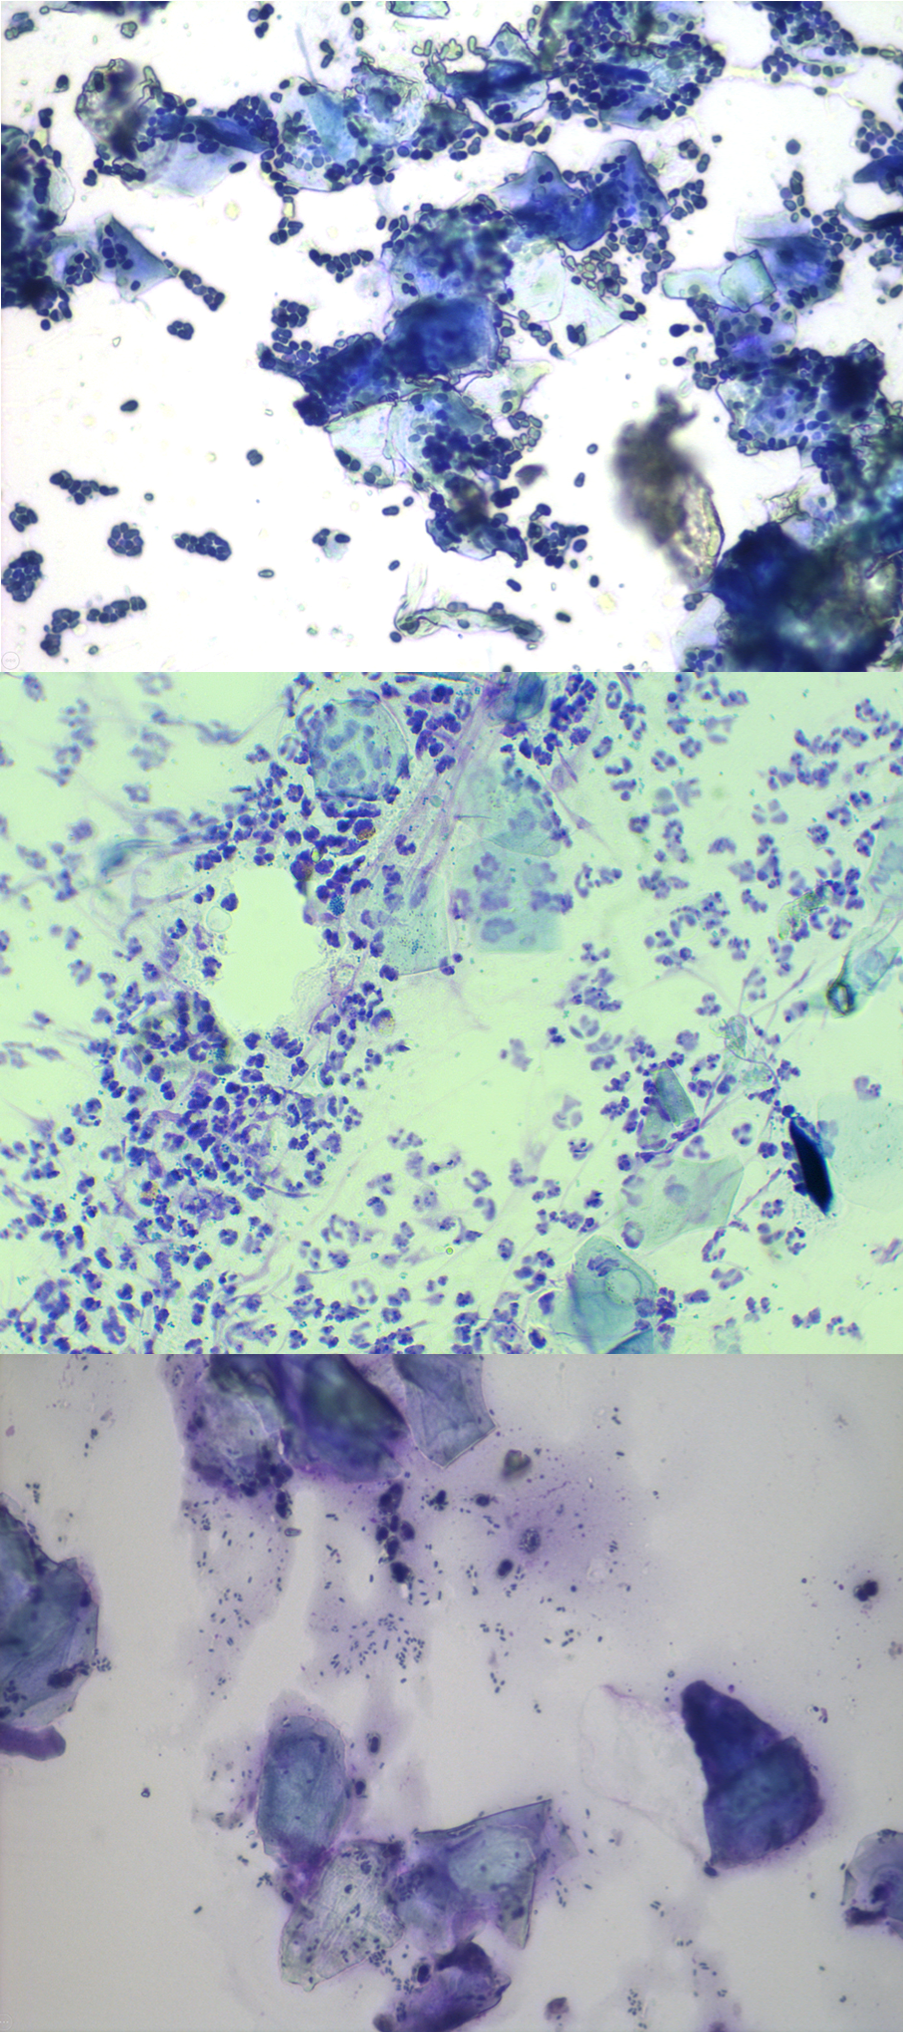

Deze beelden tonen verschillende stadia en vormen van oorontsteking.

De volgende aanbevolen stap in het onderzoek is het nemen van een staal van materiaal uit het oor van uw hond voor onderzoek onder een microscoop. Dit wordt cytologie genoemd.

Cytologie is een snelle, eenvoudig uit te voeren test die binnen de dierenartsenpraktijk kan worden uitgevoerd en die de dierenarts helpt te bepalen of er tekenen zijn van bacterië- of gistovergroei.

Met behulp van een borsteltje, een wattenstaafje of een vinger wordt materiaal uit de oren van uw hond verzameld en op een objectglaasje geplaatst. De staal wordt gekleurd met een speciale kleurstof, zodat uw dierenarts microscopisch kan onderzoeken wat er in het oor van uw hond gebeurt. Allemaal om te beslissen of er sprake is van een overgroei van bacteriën of gisten en om te zoeken naar ontstekingscellen die anders onzichtbaar zijn voor het menselijk oog.

Door een staal te onderzoeken, kan uw dierenarts niet alleen een geschikte behandeling kiezen, maar het is ook nuttig om dit proces te herhalen tijdens een controleafspraak. Er kan dan worden bepaald of de behandeling succesvol is. Ook kunnen wijzigingen in de behandeling worden aangebracht om een langetermijnplan op te stellen voor het oorprobleem van uw hond.